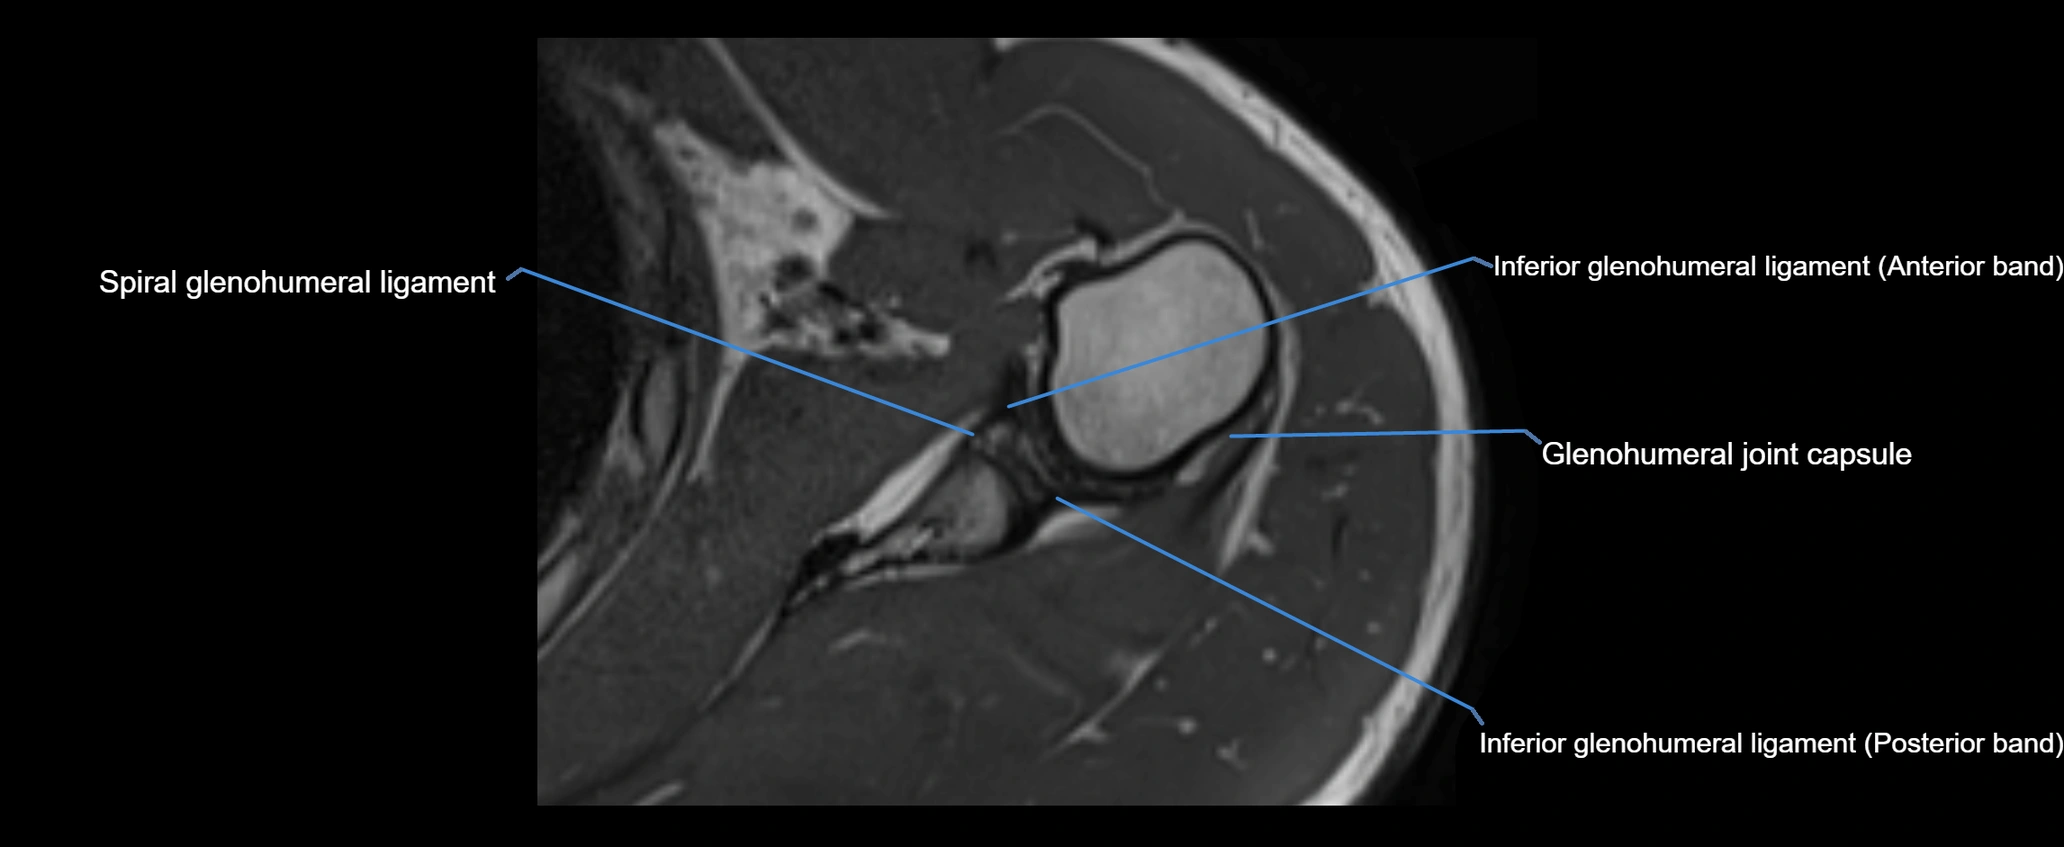

MRI Appearance

• T1-weighted images:

• Normal ligament: Low signal (dark linear band) spanning acromion to clavicle.

• Surrounding fat planes: Bright, delineating the ligament clearly.

• Marrow of clavicle and acromion: Bright due to fatty content.

• Tears: Discontinuity or irregular thickening with intermediate-to-bright signal.

• Chronic injury: Thinning, fraying, or irregular low-signal fibers with adjacent scarring.

• T2-weighted images:

• Normal ligament: Low signal, homogeneous.

• Partial tear or sprain: Focal hyperintensity or thickening.

• Complete tear: Discontinuity with fluid-bright gap between clavicle and acromion.

• Associated edema: Bright signal in distal clavicle or acromion marrow.

• STIR:

• Normal ligament: Dark linear band.

• Injury or inflammation: Bright hyperintense signal in and around ligament fibers.

• Highlights periligamentous soft-tissue edema, especially in acute trauma.

• Proton Density Fat-Saturated (PD FS):

• Normal ligament: Low signal, uniform thickness.

• Partial tear or sprain: Bright signal or contour irregularity.

• Complete tear: Clear discontinuity with bright signal gap and joint effusion.

• Excellent for assessing joint capsule, coracoclavicular ligaments, and periarticular edema.

CT image

image